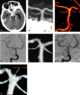

Basilar tip aneurysm

An intracranial aneurysm, also known as a brain aneurysm, is a cerebrovascular disorder in which weakness in the wall of a cerebral artery or vein causes a localized dilation or ballooning of the blood vessel. Aneurysms in the posterior circulation (basilar artery, vertebral arteries and posterior communicating artery) have a higher risk of rupture. [Source: Wikipedia ]